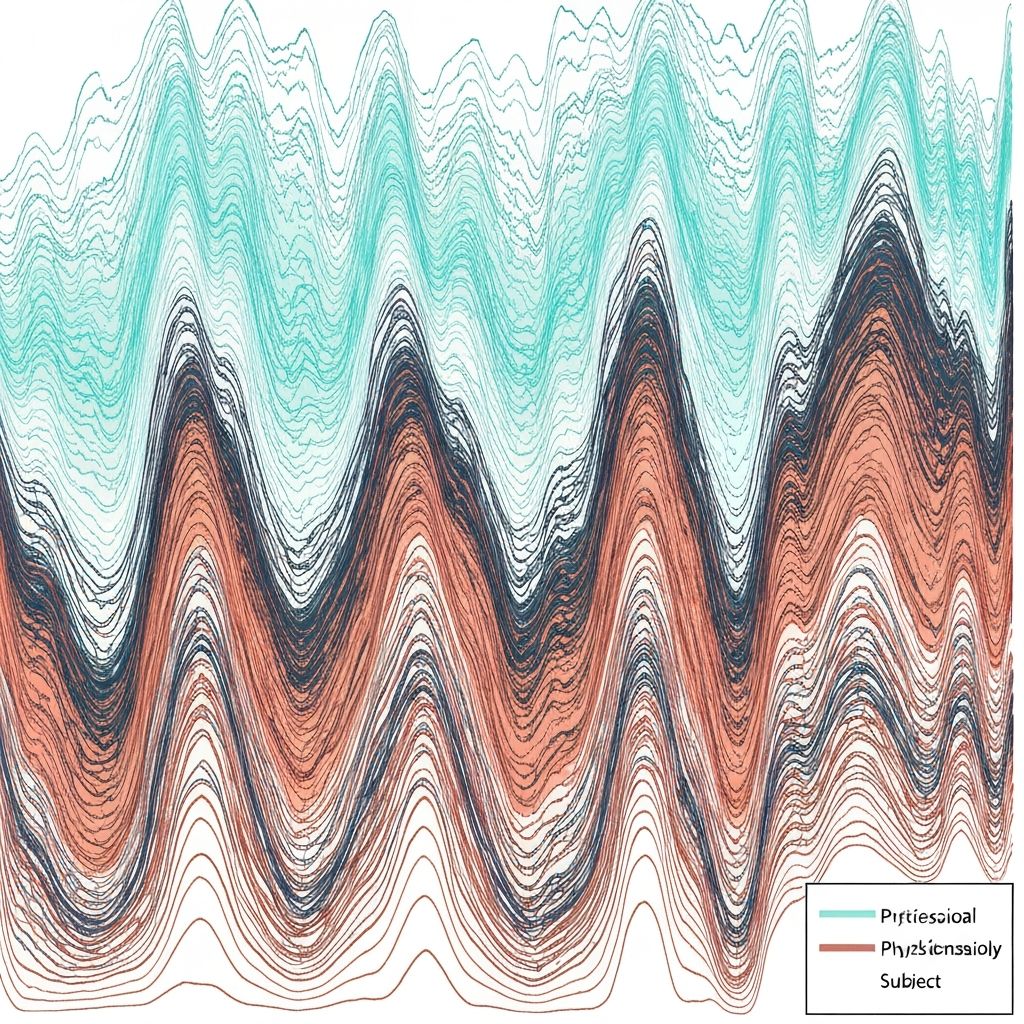

The kidneys continuously filter blood and reabsorb essential substances, including water. This process is regulated by hormones such as aldosterone and antidiuretic hormone (ADH), which respond to changes in blood osmolarity and volume. These regulatory systems ensure the body maintains appropriate fluid distribution between intracellular and extracellular compartments.